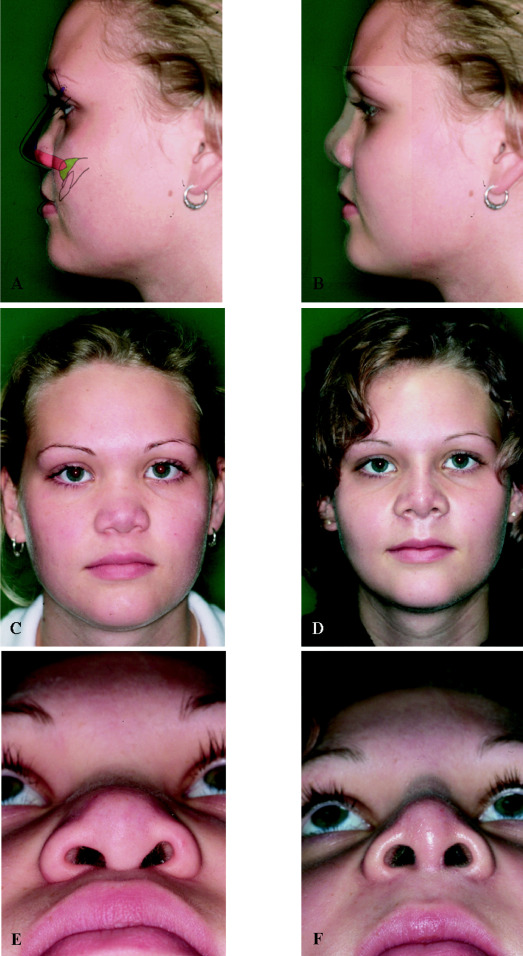

2. Cartilage or bone graft

- Cartilage, or a bone plate is harvested.

- A small graft is placed directly on the ANS.

- Recommended to be done during a rhinoplasty.

- This approach is usually paired with a projection rhinoplasty, where the surgeon grafts the dorsum, tip, and ANS. It is common in Asia and often gives great results. The extra nose projection pulls midface soft tissue forward, making the transition from the maxilla to the nose smoother whilst giving the illusion of forward growth.

The last example is especially impressive, earlier examples had grafts along the whole nose, this one used a single graft on the ANS and still pushed the nasal base forward, proof that you can fix ANS projection without touching the rest of the nose.